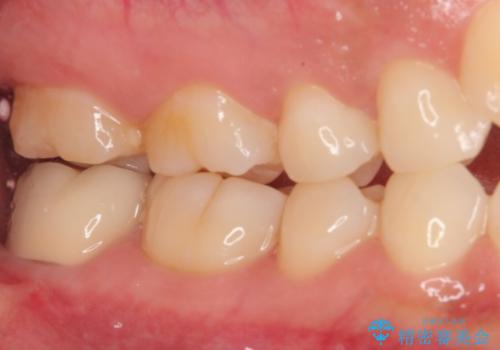

- 親知らず周りに痛みを感じるとのことで来院された患者様です。

レントゲン写真より、埋もれた親知らずの影響で手前の奥歯の歯根近くのところに大きなむし歯があることが分かりました。

まずは親知らずを抜歯し、その後手前の歯の処置を行うこととしました。

手前の歯については、痛みなどの症状は認められなかったため、神経を取り除く必要はないと判断されましたが、むし歯の場所が深いため、親知らず抜歯後に歯肉の状態が改善してからオールセラミッククラウンにて補綴治療を行うこととしました。